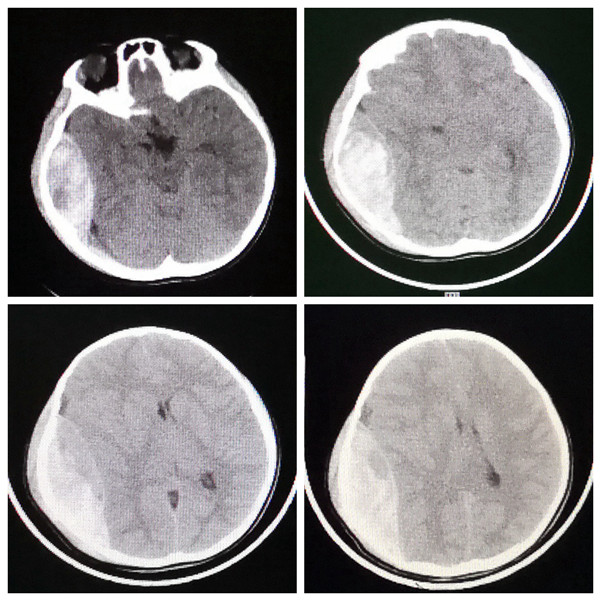

入院时患儿生命体征不稳定,呼吸节律不规则,深昏迷,双侧瞳孔散大,处于濒死状态,命悬一线。接诊的神经外科王举波主治医师立即给予20%甘露醇快速静滴,在巩守平教授、吕健主任医师指导下,迅速为患儿全方位开通绿色通道,联系影像科急诊复查头颅CT,术前影像学评估颅内出血量约110ml,同时联系麻醉手术科,并在急诊科紧急完成必需的术前准备,在麻醉手术科医护人员协助下,王举波主治医师主刀、权瑜主治医师协助,术中清除头皮下血肿80ml、颅内血肿110ml。从术前准备到入室、全麻、开颅、清除血肿、关颅,整个救治过程各个环节无缝衔接。从患儿入院至手术全部结束,共计用时不足3小时,这就是西安交通大学第二附属医院抢救危重病人的速度和效率。令人欣喜的是,患儿术后清醒,住院10天后完全康复出院,未遗留任何功能障碍,家属直呼“奇迹”!